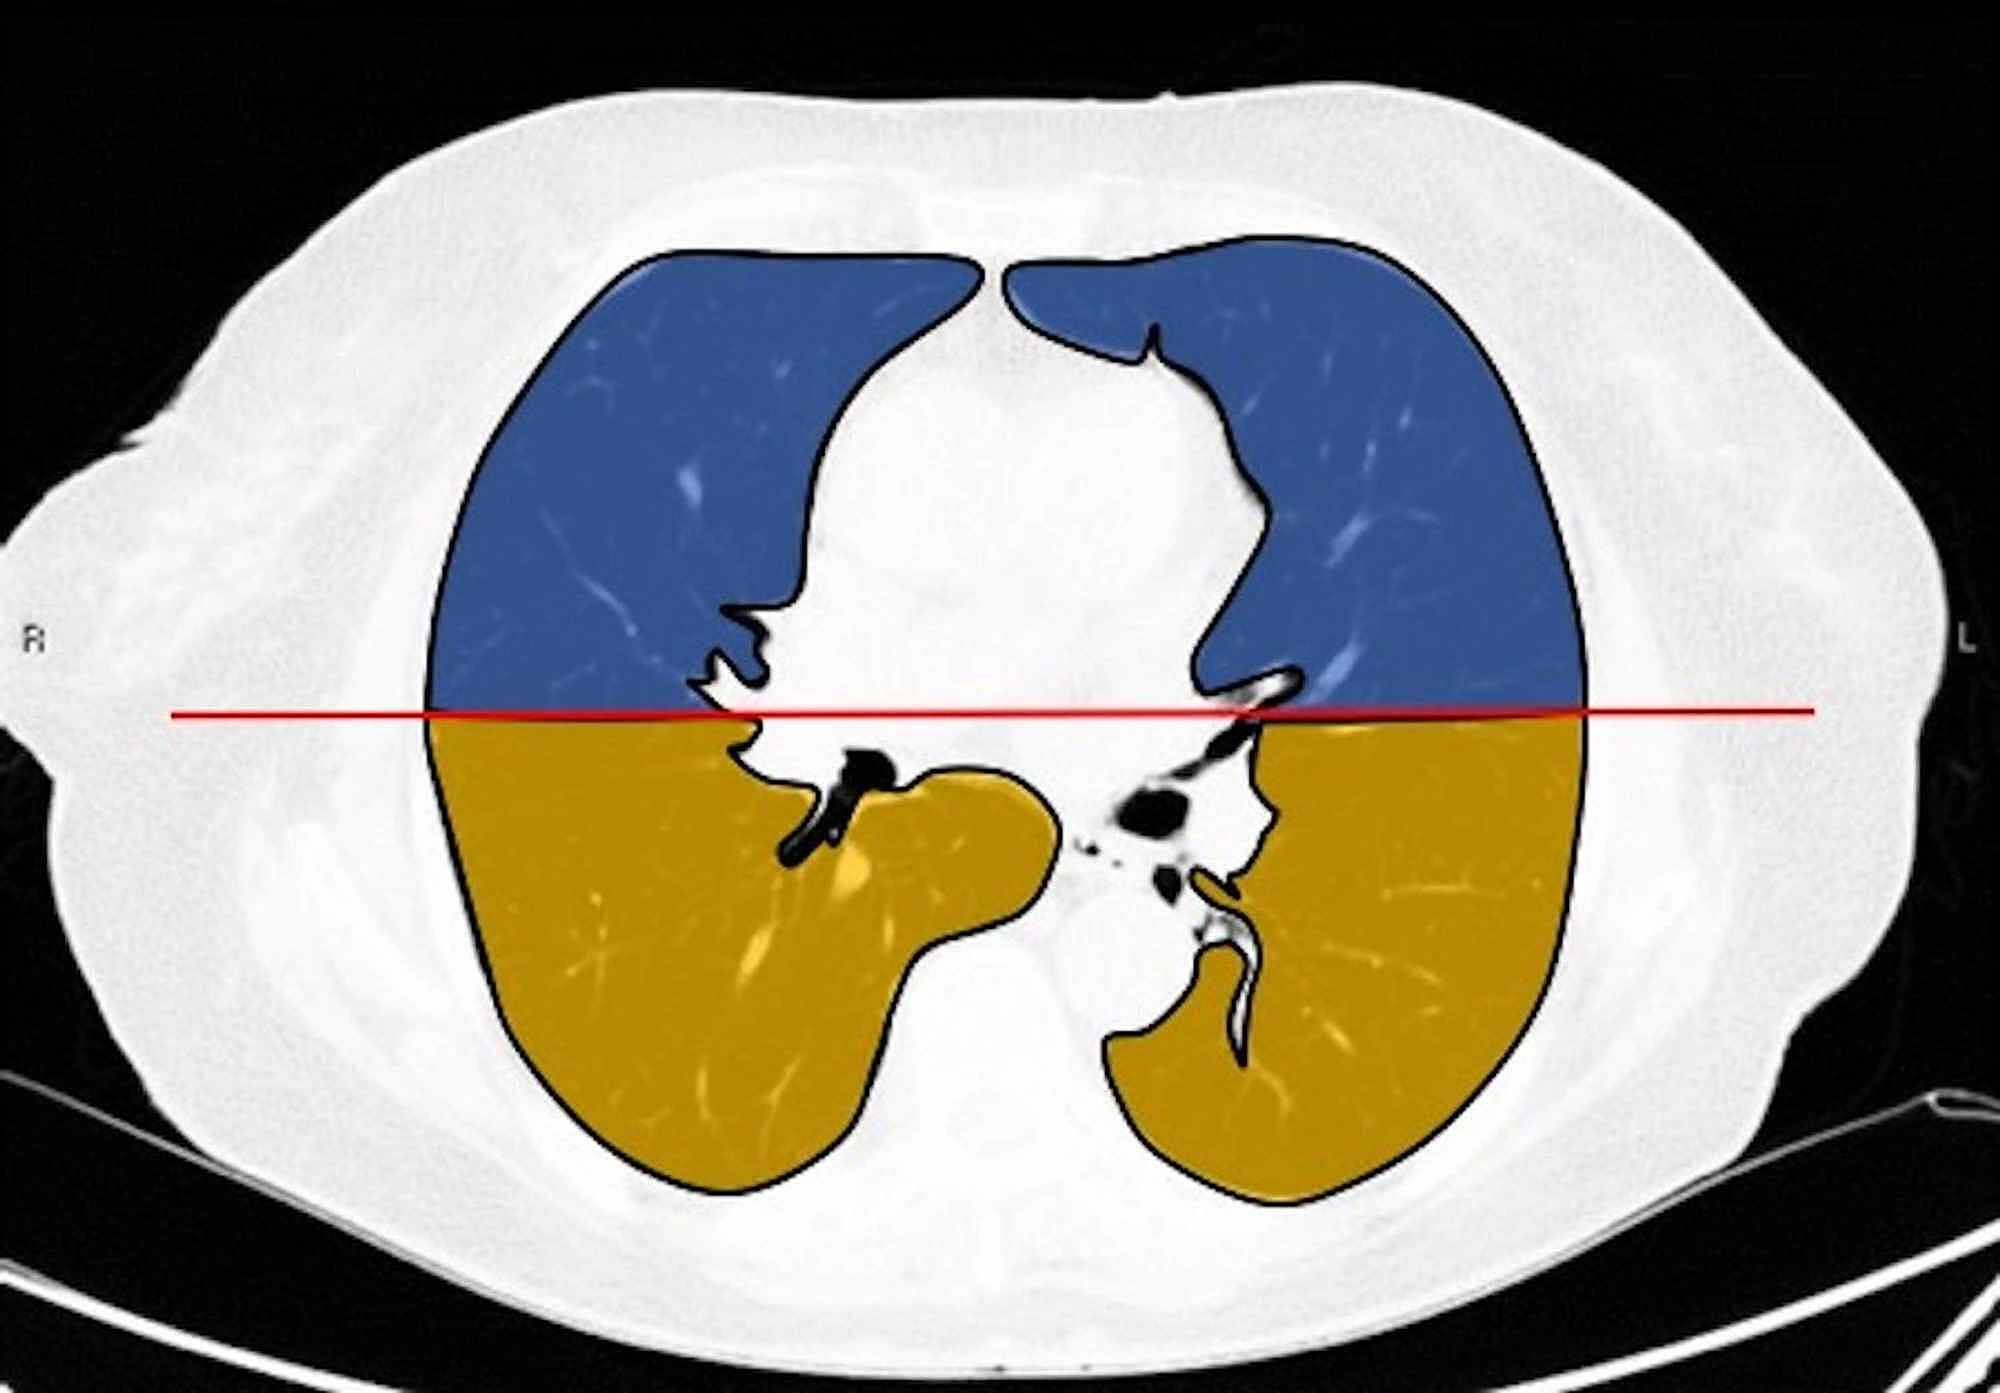

Two board-certified radiologists (E.P. and U.M., with 25 and five years of experience, respectively) reviewed the chest CT images on a picture archiving and communication system (PACS, Carestream Health, Inc, Rochester, NY). Chest CT images were evaluated with both mediastinal (width: 350 HU, level: 40 HU) and lung (width: 1500 HU, level: -500 HU) window level settings. The two radiologists identified pulmonary lesions based on their density, shape, and margin. The locations of the lung lesions were recorded as lobar, axial, anterior, and posterior. Axial locations were categorized as central (inner two-thirds of the lung) or peripheral (outer one-third of the lung). Each lung was divided by an axial line into anterior and posterior halves (Figures 2, 7). The densities of the patchy-confluent lesions were classified as pure GGO, pure consolidation, or mixed. Nodular lesion densities were classified as pure GGO, solid, or partly solid. Margins were classified as well-defined or ill-defined. As most of the lesions were patchy, confluent, and ill-defined margins, lesion sizes were not assessed. Instead, a visual severity score, which was slightly modified from Pan et al., ranging from 0 to 4 for each individual lobes was calculated. Each of the five lung lobes was visually scored on a scale of 0 to 4 as follows: 0: no involvement; 1: less than 25% involvement; 2: 25-50% involvement; 3: 50-75% involvement; and 4: 75-100% involvement.